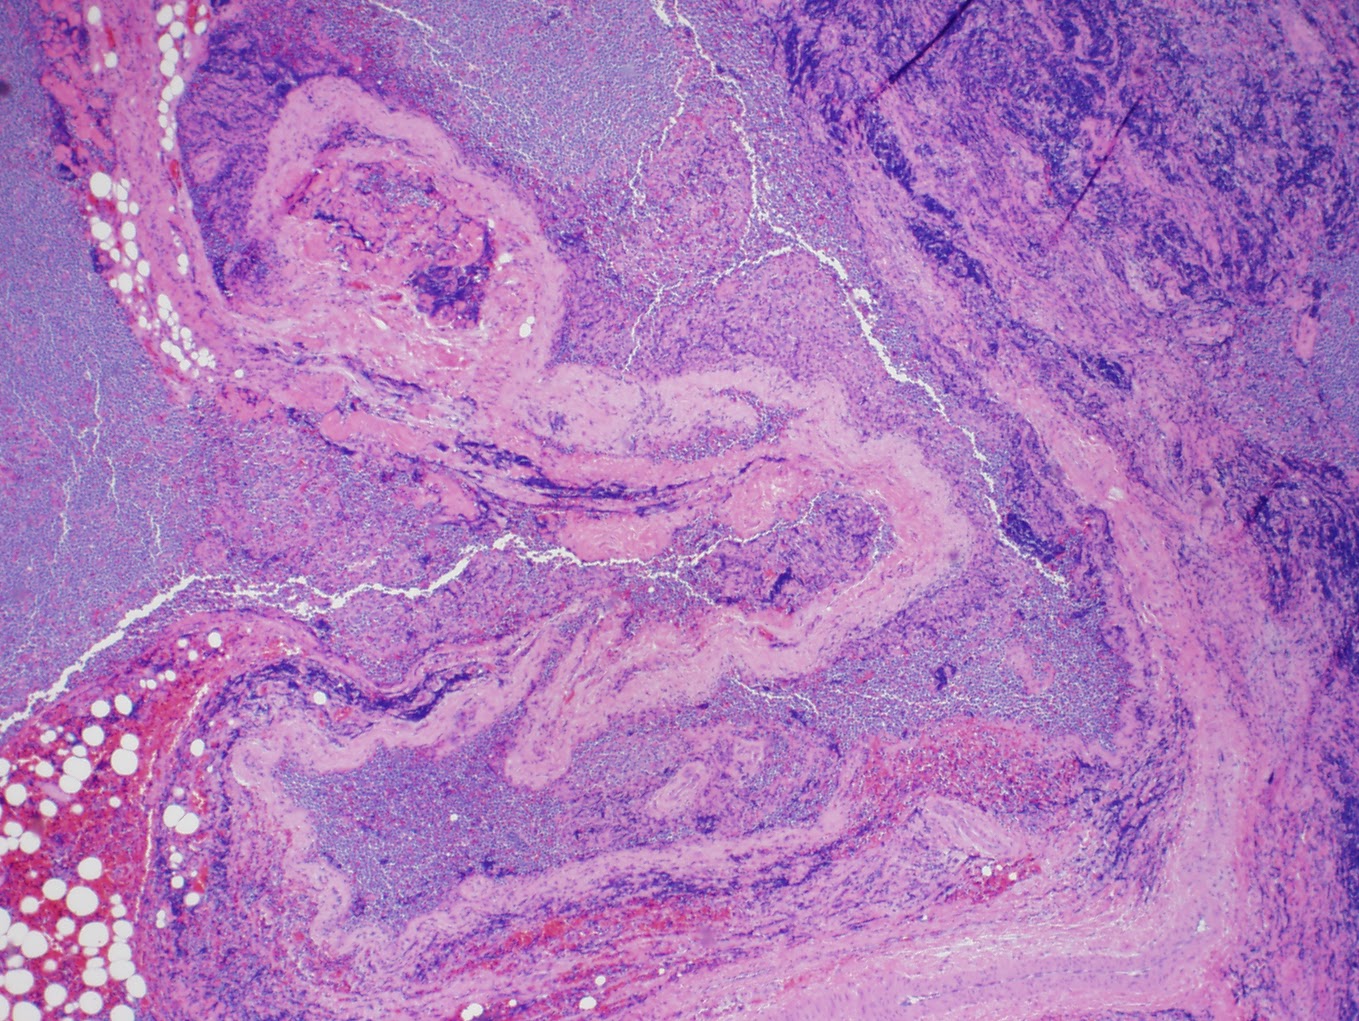

T-CELL LYMPHOBLASTIC LYMPHOMA

One of DIllon's first questions when he came out of surgery was...."Can I see the lymph nodes?" The surgeon told him that it was not possible to see the actual lymph nodes but that he could try to get photos of the slides from the lab where the biopsy analysis was taking place. Dillon was satisfied with that and wanted you all to see what the monster growing in his neck looks like under a microscope.

One of DIllon's first questions when he came out of surgery was...."Can I see the lymph nodes?" The surgeon told him that it was not possible to see the actual lymph nodes but that he could try to get photos of the slides from the lab where the biopsy analysis was taking place. Dillon was satisfied with that and wanted you all to see what the monster growing in his neck looks like under a microscope.